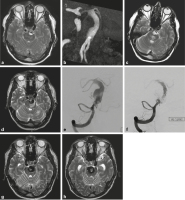

Abbildung 3a-h: Der 68-jährige Patient erlitt im Mai 2019 eine erstmalige Hirnstammischämie mit reversiblem neurologischem Defizit. Das MRT (a) zeigte ein teilthrombosiertes fusiformes Aneurysma der A. basilaris (b). Im Oktober 2019 erneute Hirnstammischämie mit bleibender Hemiparese, das Aneurysma hatte sich vergrößert, der thrombosierte Anteil hatte zugenommen (c). Bis November 2019 hatte die Hemiparese deutlich zugenommen, das Aneurysma hatte sich weiter vergrößert; es bestand nun ein ausgeprägtes Perifokalödem in der Brücke links (d). Es folgten Stentimplantationen (Leo 5,5 × 70 mm, Balt Germany, Düsseldorf, Deutschland; p64 5 × 24 mm, Phenox, Bochum, Deutschland), teilweise Ausfüllung der Einstromzone des Aneurysmas mit Coils und Verschluss des linken Schenkels der fenestrierten linken Arteria vertebralis in mehreren Sitzungen (e, f). Im Juni 2020 war angiographisch der Einstrom weitgehend unterbunden (f) und die MRT-Kontrolle zeigte das Hirnstammödem rückgebildet (g). Klinisch war der Patient stabil, aber die MRT-Kontrolle zeigte eine weitere Größenzunahme des Aneurysmas (h).